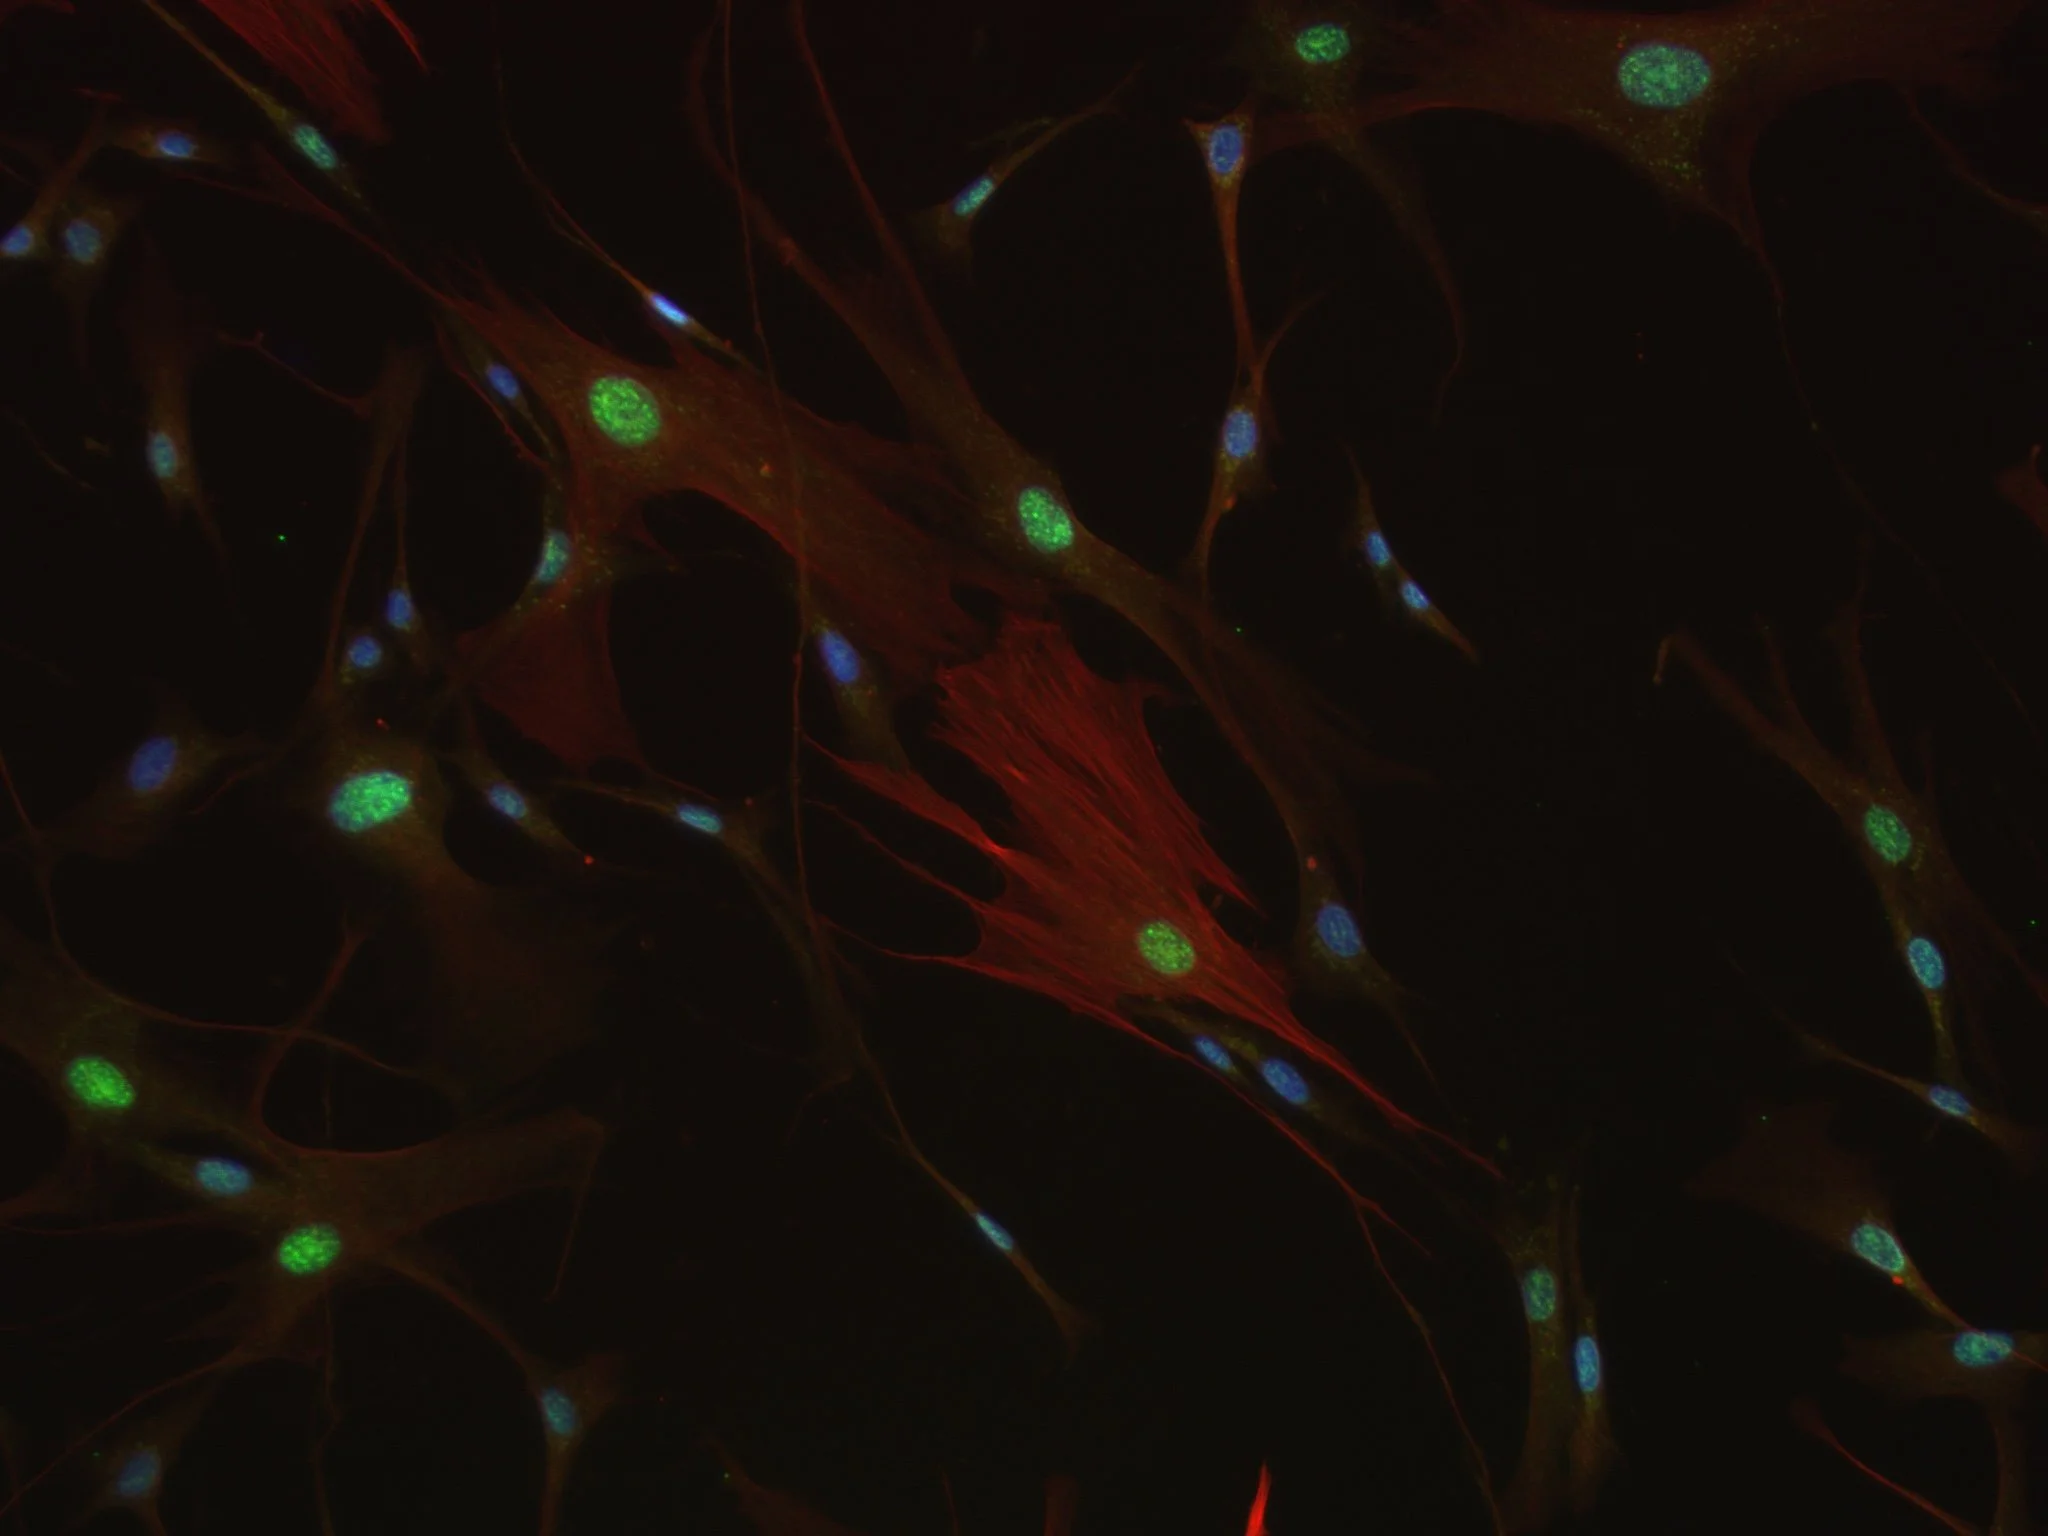

Figure 1: Activated myofibroblasts in the lungs are shown in green. Muscle protein is shown in red. Image courtesy of Dr. Hagood.